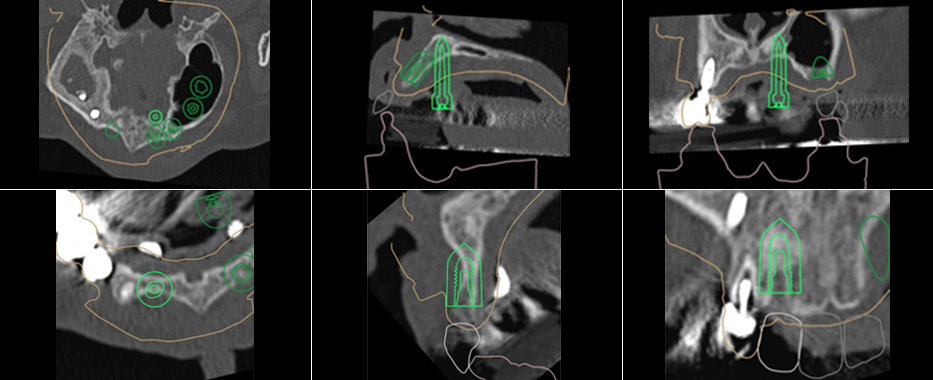

3D CT를 통한 정밀 진단

3D-CT를 통해 다각도로 진단하여 환자의 골조직, 주변 치아의 위치, 신경 위치 등의 해부학적 요인들을 정확히 파악합니다.

컴퓨터'모의수술'수행

3D-CT의 정보와 상담한 내용을 바탕으로 최적의 임플란트 식립 위치를 계획합니다.